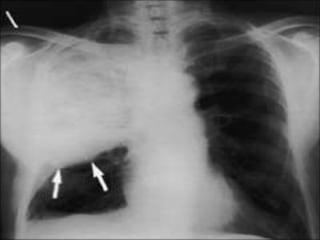

DEEP SULCUS SIGN

• The deep sulcus sign describes the radiolucency extending from the lateral

costophrenic angle to the hypochondrium

• It is an important clue indicating possible pneumothorax in chest x-rays obtained in

the supine position.

• When plain films are taken with the subject in an upright position, the free air in the

pleural space gathers at the apicolateral space.

• In the supine position, the air accumulating at the anterior space forms a triangular

radiolucency that makes the inferior borders of the lateral costophrenic angle

conspicuous

DEEP SULCUS SIGN •The deep sulcus sign describes the radiolucency extending from the lateral costophrenic angle to the hypochondrium • It is an important clue indicating possible pneumothorax in chest x-rays obtained in the supine position. • When plain films are taken with the subject in an upright position, the free air in the pleural space gathers at the apicolateral space. • In the supine position, the air accumulating at the anterior space forms a triangular radiolucency that makes the inferior borders of the lateral costophrenic angle conspicuous